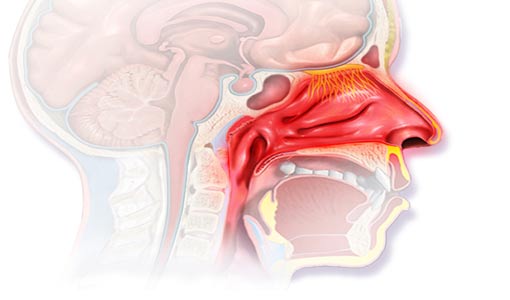

يجمع الأطباء على أن تعدّد مسبّبات حساسية الأنف، وكثرة المواد المهيّجة، عاملان يفسّران شيوع ذلك النوع من الحساسية، التي تعدُّ من أكثر أمراض الأنف والأذن والحنجرة انتشاراً. وبما أن أعراضها تشبه الرشح، لا يندر أن يخلط البعض بينهما.

حساسية الأنف حالة شائعة جدّاً. إذ ثمّة جزيئات متعددة مُهيّجة لهذا النوع من الحساسية. لذا، يؤكد أطباء الأنف والأذن والحنجرة ("ENT" بالإنجليزية، أو "ORL" بالفرنسية)، أنّ نحو نصف مُراجعيهم يستشيرونهم بسببها. هكذا، نظراً إلى تعدّد الأسباب، تشير إحصاءات "منظمة الصحة العالمية"، إلى أنّ حساسية الأنف (allergic rhinitis بالإنجليزية، وrhinite allergique بالفرنسية)، عالمياً، تصيب 25 في المئة من المراهقين والبالغين في سن أقل من 50. والرقم يشمل نوعي حساسية الأنف الاثنين كليهما، وهما:

أما الأعراض، فهي على الأغلب متشابهة للنوعين المشار إليهما كليهما (الحساسية الدائمة أو المؤقتة). مثلاً، عند المصاب بحساسية ضد بعض أنواع غبار طلع النباتات، تكون الأعراض كالآتي:

- تظهر نوبة العطس وحك الأنف، وهَرْشه، بسرعة خاطفة حالما يدخل المصاب حقلاً يضم تلك النبتة، أو مجرد مروره قريباً.

- يَنْسَد منخارَا الأنف كلاهما. وتعتري المصاب رغبة شديدة في هرش الأنف وحكّه.

- يسيل صباب مائي من الأنف.